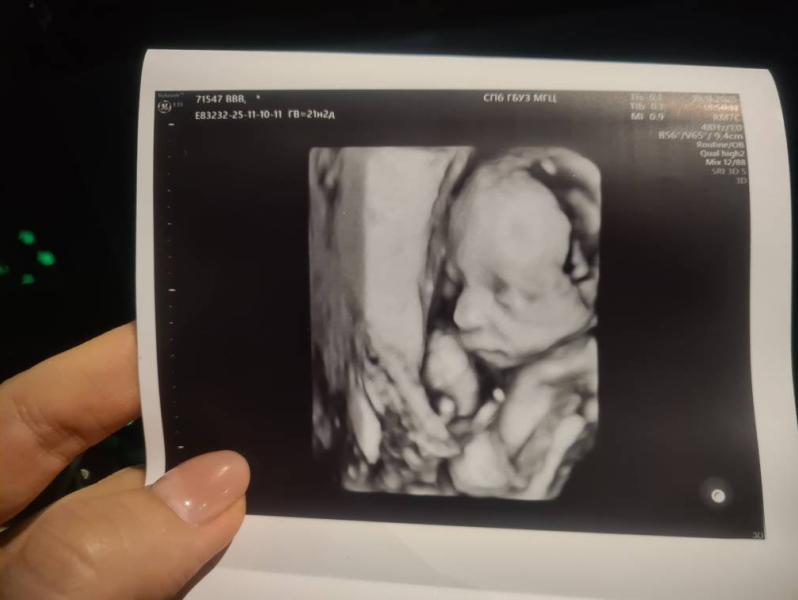

И мне ещё сделали 3D снимочек, божечки, я не могу 😭😭😭 ну какая она сладкая, а носик у неё папочкин!!

Сходила в МГЦ сегодня, делали УЗИ такое подробное, какое нигде не делали. Лежала там аж 50 минут 🫣 каждый орган, каждую косточку осмотрели, замерили, проверили, перепроверили 🥺 по размерам доченька меньше своего срока, по весу сильно меньше, но я стараюсь не грустить, надеюсь, что ещё догонит 🙏

Почки все таки изначально было две, но они срослись и получилось, что они оказались на одной стороне 🫢 УЗИст сказала, что функционирует все нормально, в целом все хорошо! Ещё ждёт приём гинетика после этого УЗИ, а затем через месяц снова УЗИ у них, чтобы проверить в динамике мою крошечку ❤️

Кровотоки в порядке, по всем параметрам (кроме веса) она +- хорошо растёт 🙏 все косточки, размер головки и так далее... Просто маленький ОЖ и видимо от этого такой маленький вес(